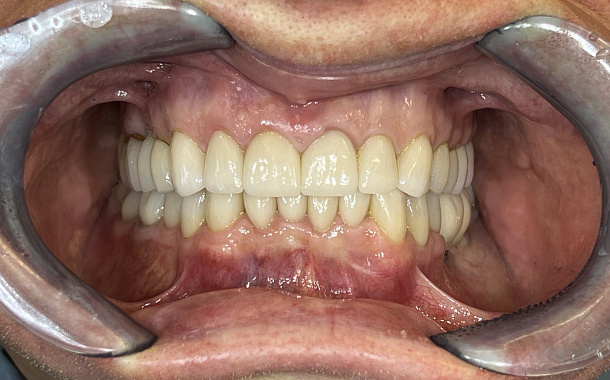

Высочайшая точность для идеальной посадки

Aoralscan 3 обеспечивает сканирование с точностью до 6,9 мкм, что позволяет создавать максимально точные цифровые слепки. Это критически важно для изготовления коронок, мостов, виниров и других ортопедических конструкций, гарантируя их идеальную посадку и долговечность.Скорость и комфорт для пациентов

- Минимизация погрешностей: Высокая точность сканирования снижает риск ошибок при изготовлении протезов и реставраций.

- Максимально точные и эстетичные ортопедические конструкции

- Долговечные результаты